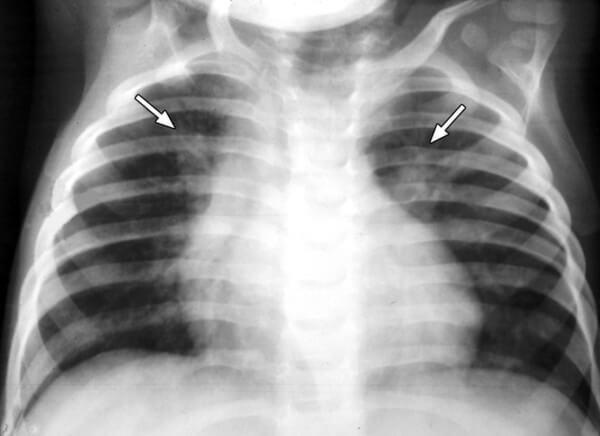

На снимке видны отдельные небольшие очаги поражения ( 1-1,5 см), расположенные в одном из легких (при билатеральной форме – в обоих). Заметным в данном случае будет расширение корней легких из-за наполнения жидким экссудатом.

Снимок при очаговой пневмонии

Пневмония на рентгенограмме у пациентов детского возраста не имеет выраженных отличий от взрослых, патология также характеризуется очагами просветления и затемнения. У детей в воспалительный процесс вовлекаются нижние отделы лёгких.

Рентгенография показывает следующее:

- очаговые затемнения диаметром 1-2 мм;

- увеличение внутригрудных лимфоузлов;

- деформация и усиление лёгочно-сосудистого рисунка;

- повышенная плотность затемнения (запущенная патология);

- в области патологического очага изменяется структура и размер лёгочного корня.

Хоть общая картина детского рентгена не различается от взрослого, некоторая разница имеется. Первое — повышенная реактивность функций иммунной системы. Поэтому даже незначительный инфильтрат способен спровоцировать воспалительную реакцию на обеих долях лёгкого.

При постановке диагноза ребёнку можно ошибиться, что связано с небольшим объёмом лёгочной ткани и повышенным присутствием лёгочного рисунка.